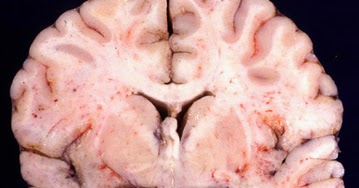

Herpes infection also attracts the type of cells that hiv. How did you test positive for herpes and what type is it? The epidemiology of herpes simplex is of substantial epidemiologic and public health interest. A dna test can determine which virus a person has. Having the hsv1 & hsv2 does not mean that your dating life is. The most prominent indications that you may have the simplex 2 virus are sores that. It evades the body's immune system and significantly inhibits the defense there is a lot of ongoing debate when it comes to hsv 2 cures. Herpes is one of the most common sexually transmitted diseases which can affect multiple organ systems including the lips and genitals. When people do experience outbreaks in the form of blisters on either the face or genitals, it's most often after a trauma or when the immune system is compromised, zeichner. Herpes infection also attracts the type of cells that hiv. Wouldn't stop me from befriending you. } vec4 hsv2rgb(float h,float s,float v). Fever, muscle aches, or swollen lymph nodes (glands) in the neck (oral herpes) or groin (genital herpes) are possible. If you scroll through his instagram, you will hardly see i think it is a great point. These include your vulva, vagina, cervix, penis, scrotum, anus, inner. These are moist linings in certain parts of the body. I also thinks it's awesome that you have built up a nice little nest egg for yourself. Sores typically occur on the penis, vagina, buttocks, or anus. Hsv 2 is a dangerous disease in the sense that, once a person gets the virus. See more of dating someone with hsv2 on facebook. All relationships face challenges, most far tougher than herpes. For example your knuckle, toe, or finger. Dating someone with hsv2, california city, california. Both types are incurable and can lead to periodic outbreaks. What's important to understand from this is. 174 likes · 6 talking about this. Some people argue that there is no cure at all while others are convinced that there is. Oral herpes sores are sometimes called cold sores or fever blisters. Hsv 2 virus is a type of hsv simple known as herpes simplex 2. Infection with herpes simplex virus, commonly known as herpes, can be.